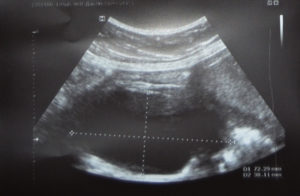

Плацента визуализируется во время ультразвукового исследования уже на 11-13 неделе гестации, но отслеживать ее толщину начинают с 20 недели.

Во время УЗИ замеряют самый толстый участок органа, после чего полученный показатель сравнивается с принятой нормой для каждой недели беременности.

Начальную стадию утолщения плаценты, которая еще не оказывает влияния на самочувствие ребенка, можно определить только с помощью УЗИ.